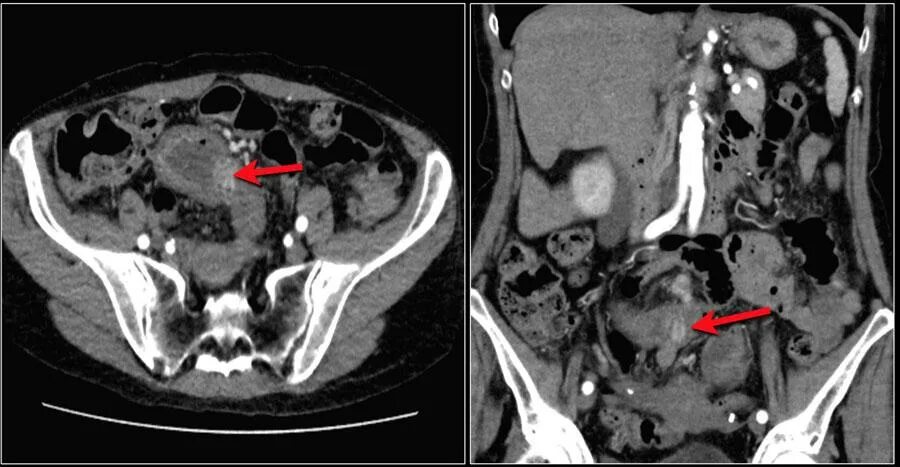

Метастазы при раке сигмовидной кишки